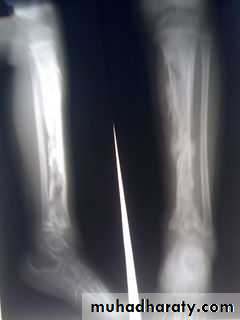

Necrosis: a week, bone death, and Pieces of dead bone may separate (Sequestra) varying in size.

New bone formation: by the end of 2nd week, from stripped periosteum (involucrum), enclosing the sequestrum and infected tissue. If the infection persists, pus and tiny sequestrae may discharge through perforations (cloacae) in the involucrum and track by sinus(es) to the skin surface.

Plain X-ray: obvious by the end of 2nd week: diffuse rarefaction, then periosteal new bone formation, then squestrum, but treatment should not be delayed until x-ray changes appear.Ultrasonography: may detect a subperiosteal collection of fluid in the early stages of osteomyelitis.